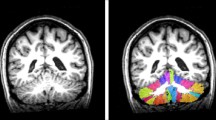

The anatomical automatic labeling brain atlas template was used to quantificationally extract cerebral region volume of the regions of interest (ROIs) based on automated MRI brain volumetry system (www. volbrain.upv.es). The ROIs for cerebral region volume quantization were as follows: (1) bilateral frontal lobes; (2) bilateral parietal lobes; (3) bilateral occipital lobes; (4) bilateral temporal lobes; (5) right middle frontal gyrus; and (6) left caudate. The decision to analyze the left caudate and right middle frontal gyrus as ROIs was guided by the results from voxel-wise statistical analyses. Additionally, cerebellar segmentation was performed to quantify cerebellar lobule volumes based on CERES software. A total of 26 cerebellar lobules were obtained considering left and right hemispheres: white matter and lobules I–II, III, IV, V, VI, Crus I, Crus II, VIIb, VIIIa, VIIIb, IX, and X. The pipeline for cerebellum segmentation and normalization was previously described [24].

VBM-and ROI-based brain MRI comparisons between the CI and CP subgroups

The VBM analysis indicated that the CI subgroup had lower GM volume in brain regions including the cerebellum, left caudate nucleus, and right middle frontal gyrus (peak t value = 4.39, P < 0.05, FDR-corrected at cluster level). The cerebellar lobules with decreased volume in the CI subgroup included bilateral lobule VI, right lobule Crus I, right lobule IV_V, and right lobule III (Fig. 2A and Fig. S1).

Cerebellar volume(s) loss in SCA3 patients with cognitively impaired (CI subgroup) and correlation with impairments of cognitive function/emotional performance/motor function. A Voxel-based morphometry analysis of gray matter volume among the segmented cerebellar lobules of CI subgroup compared with CP subgroup. Results were displayed on a standard cerebellar template; P < 0.05, the false discovery rate corrected at the cluster level. Color bar represents t values. B Pearson’s correlation analysis between cerebellar lobule volumes and test scores of cognitive functions (based on the modified MACFIMS tests), emotional performance (based on the HDRS and HARS), and motor function (based on ICARS), Results were presented with the adjusted r value. Correlations with statistical significance were emphasized with black frames (P < 0.05) and green frames (P < 0.01). CERE = cerebellum; CI = cognitively impaired; COWAT = controlled oral word association test; CP = cognitively preserved; CVLT-II DR = California verbal learning test-second edition, delay recall; CVLT-II TL = California verbal learning test-second edition, total learning; HARS = Hamilton anxiety rating scale; HDRS = Hamilton depression rating scale; ICARS = international cooperative ataxia rating scale; JLO = judgment line orientation; L = left; MACFIMS = minimal assessment of cognitive function in multiple sclerosis; PASAT 2 s = paced auditory serial addition task-2 seconds; PASAT 3 s = paced auditory serial addition task-3 seconds; R = right; SCA3 = spinocerebellar ataxia type 3; SDMT = symbol digit modalities test

Volume quantification bases on ROI measurement indicated that the CI subgroup had lower volumes in the left caudate nucleus (P = 0.010), in the whole cerebellum (P = 0.004), and in several segmented cerebellar lobules, including bilateral lobule VI (P = 0.004 for left and P = 0.005 for right), right lobule crus I (P = 0.040), right lobule III (P = 0.009), and right lobule IV (P = 0.007). No other differences were detected in the ROI-based analysis (Table S5 and Table S6).